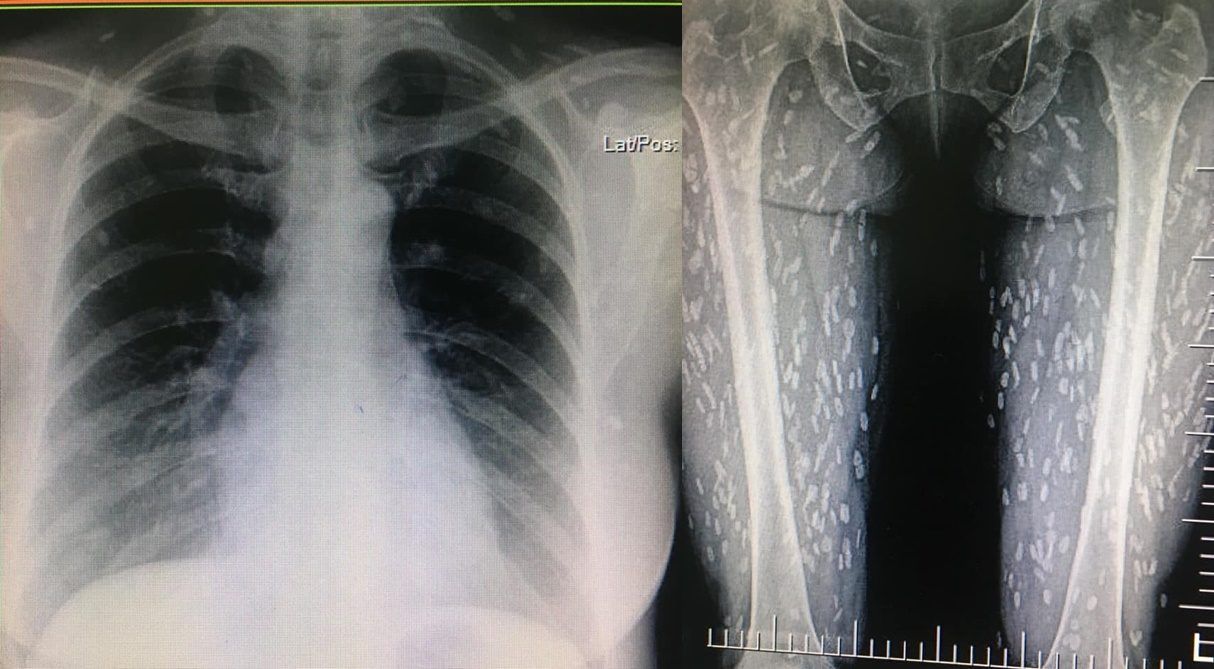

พยาธิตืดหมูกำลังเป็นที่สนใจในโลกโซเชียลเป็นอย่างมาก หลังจากที่สมาชิกเฟซบุ๊ก Kwang Volemage ได้โพสต์ภาพจากฟิล์มเอกซเรย์ผู้ป่วย ซึ่งพบว่าภาพจากฟิล์มแสดงให้เห็นพยาธิตืดหมูจำนวนมากที่แทรกอยู่ในชั้นผิวหนังของร่างกาย เต็มไปหมดทั่วทั้งขาของผู้ป่วย ซึ่งเกิดจากการกินเนื้อหมู หรือ เนื้อวัว สุกๆ ดิบๆ รวมทั้งแหล่งน้ำธรรมชาติที่ไม่ผ่านความร้อน และ ผักที่ไม่ได้ล้างจนสะอาด ซึ่งคุณหมอยังบอกอีกว่าเคยเห็นเคสนี้จากตำราไม่คิดว่าจะมาเห็นของจริง

โพสต์ดังกล่าวระบุว่า “cc : หายใจลำบาก คอไม่โล่ง มีเสมหะในคอ O2sat 98% lung – clear pharynx not inject  me : คิดในใจไป CXR หน่อยก็ได้

แล้ว film ก็มา เลยไป film femur ต่อ ตามคำแนะนำ Supanat Boonneramitr #อึ๊ยยยยคนลุกกกกก ~~~~~~ #cysticercosisจากหนังสือมาสู่ของจริง #พยาธิตืดหมู”

โดยเพจ Drama-addict ได้อธิบายว่า ภาพทางขวาที่เห็นนั้นเป็นภาพ xray บริเวณขา และสะโพก ส่วนที่เห็นเป็นขาวๆ กระจายไปทั่วๆ กล้ามเนื้อคือตัวอ่อนพยาธิตืดหมูที่ชอนไชเข้าสู่ร่างกาย หลังจากที่เหล่าพยาธิตัวอ่อนมันเข้าไปในร่างกาย มันก็อาจจะลุกลามไปแถวกล้ามเนื้อหรือเข้าสมอง จากนั้นก็จะกลายเป็นหินปูนแบบที่เห็น ซึ่เป็นกลไกของร่างกายที่จะพยายามจะทำให้พยาธิตายลง และเมื่อเกิดเห็นปูนก็แสดงว่าพยาธิตายแล้ว แต่สิ่งเกิดขึ้นเป็นหินปูนที่คล้ายๆ แผลเป็นในสมอง แผลเป็นตัวนี้จะเป็นปัญหาระยะยาว บางคนที่ไชเข้าสมอง ก็จะไปหาหมอด้วยอาการ ปวดหัวเรื้อรัง ชักเกร็ง สำหรับการรักษาก็มีตั้งแต่การกินยาฆ่าพยาธิจนถึงผ่าตัดเอาตัวอ่อนออก